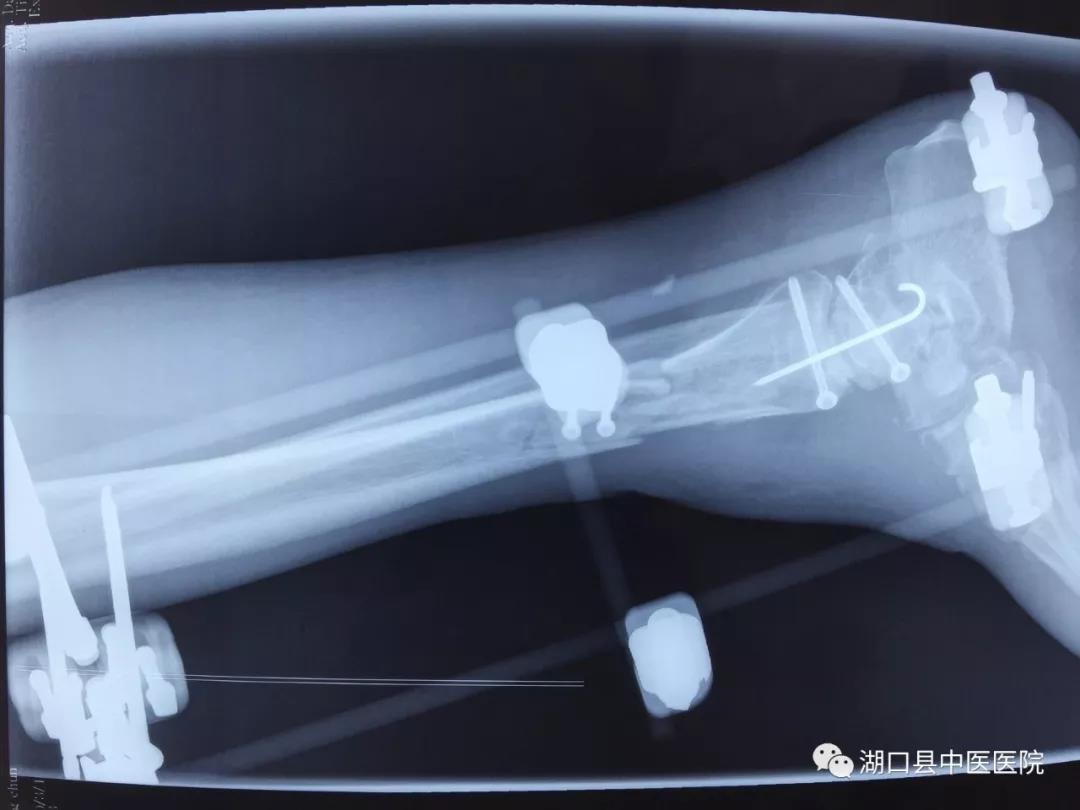

时间回到今年1月4日。晚间10时左右,刚做了2台急诊手术正准备休息的吴学峰医师接到急诊电话,有一名严重车祸伤患者,右下肢伤势严重,请求会诊。吴医生放下电话,急忙赶到急诊科。现场一看,患者周大叔伤情非常严重,右小腿被碾压得血肉模糊,受伤部位骨头外露,面色苍白,烦躁不安。血压80/50mmHg,肢体远端冰凉干瘪,摸不到血管搏动。病情之棘手超乎想象:一是伤者右下肢系车轮重物碾压后不全离断,皮肤软组织损毁严重、部分缺失,胫骨中下段、距骨、跟骨粉碎性骨折伴踝关节脱位;二是血管神经肌腱碾压离断,血管缺损;三是伤处沾满泥沙,污染严重。面对这些不利情况,通常来说进行截肢手术是最为稳妥的办法:手术难度低、过程短、风险小、费用低、后期并发症少。

按照预定计划,手术有条不紊地进行着,骨折的外固定支架临时固定,在显微镜下进行血管、神经的逐一吻合,肌腱的修复……经过6个多小时的持续作战,次日凌晨5时许,周大叔离断的下肢逐渐恢复红润,断肢再植术完成,手术成功。在骨伤科医护团队的密切配合和不懈努力下,经过抗凝、解痉、抗感染等治疗措施,右小腿血运良好,一期肢体成活。在周大叔住院期间,骨科专家柯阳春院长始终惦念着他的病情,经常来到病房看望了解情况。二期周大叔由于外伤导致踝关节周围皮肤缺损,胫骨及肌腱外露同时伴有感染,传统的植皮方法无法解决问题。骨伤科团队在柯院长主持下经过讨论后,决定应用显微外科技术吻合血管的游离股前外侧皮瓣修复创面,周大叔得以顺利康复出院。经了解,此例游离皮瓣修复创面为湖口县首例。